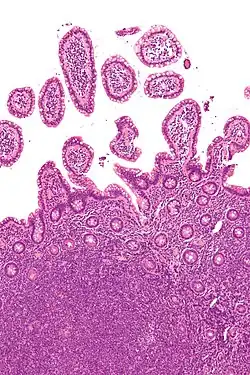

Non-Hodgkinovy lymfomy (zkráceně NHL) je skupina onemocnění způsobujících rakovinu krve, která zahrnuje všechny lymfomy kromě Hodgkinových. Různé NHL se velmi liší v nebezpečnosti, od nebolestivých po velmi agresivní.